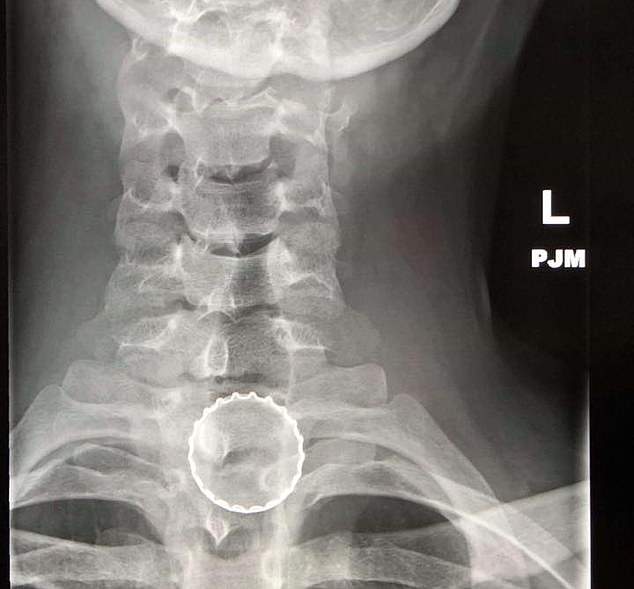

喉嚨

・遙控器

・保險套

・堅果

・激光筆

・塑膠製的玩具劍

・保險絲

・冰淇淋蓋子

・助聽器

・膠囊

・拼圖

・鑰匙

・鑽頭

・口香糖

・聖誕節裝飾物